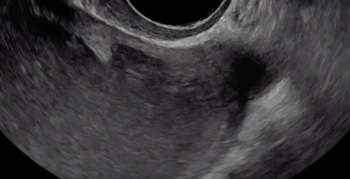

The beginning of the clip depicts a thin hyperechoic layer just deep to the vagina, which represents the rectouterine pouch peritoneum.

Following the hypoechoic layer of the bowel wall throughout the clip, viewers can appreciate the consistency of the thickness and echogenicity of this layer.